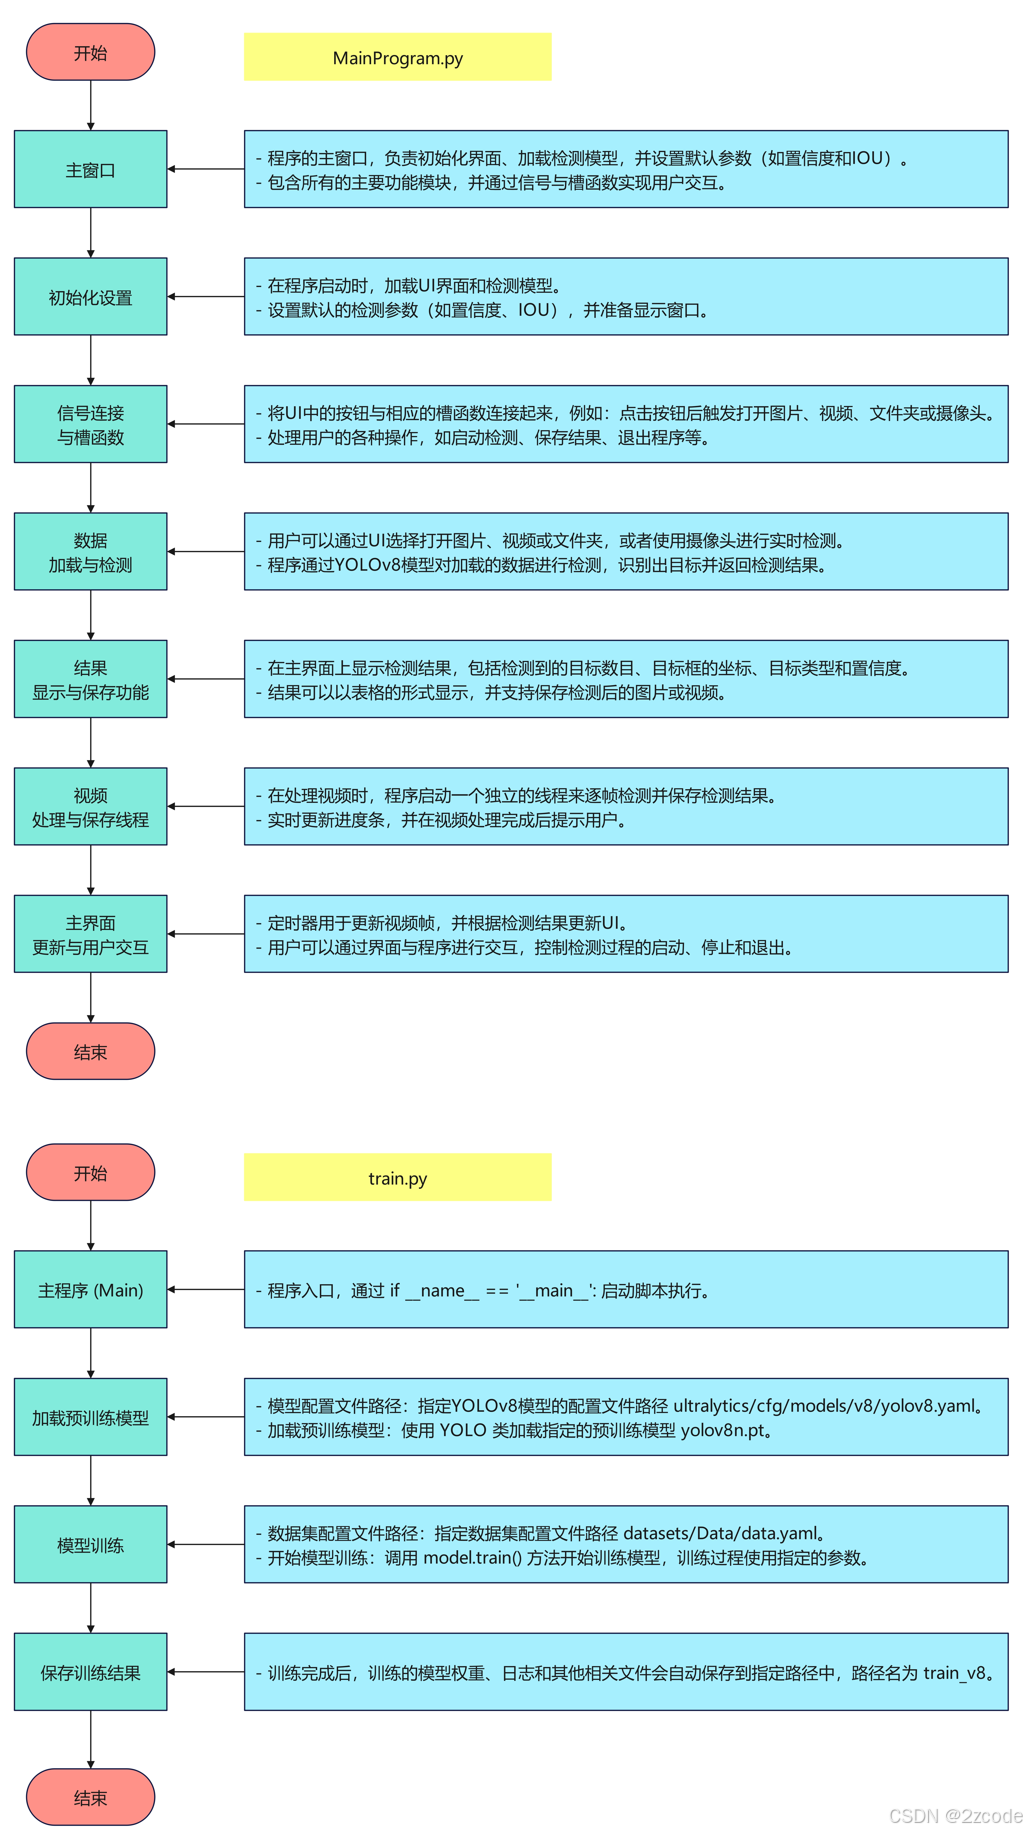

算法流程

仅对train.py部分代码简要讲解。该项目可以按需有偿讲解,提供后续答疑。